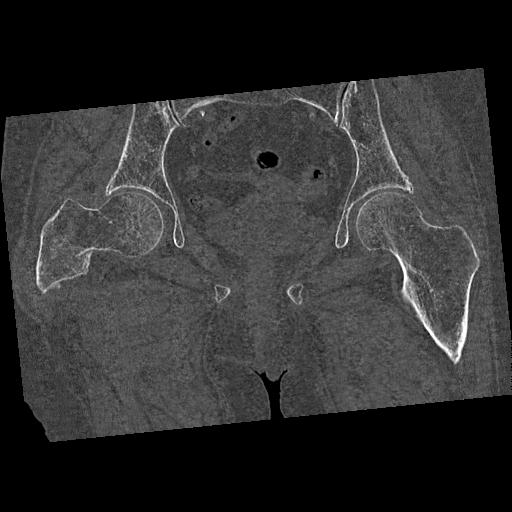

110286 2/17 股関節 2R 74歳女性 右人工骨頭